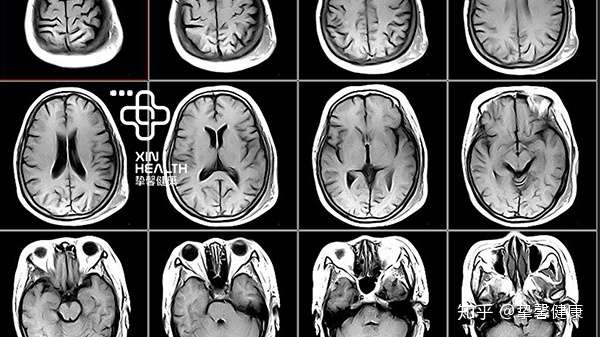

写给小白 关于体检中核磁共振mri 科普 知乎

脑部磁共振图片 第1页 要无忧健康图库

高清mri图 颅脑磁共振mri解剖

脑部磁共振检查什么 脑部磁共振检查多少钱 第二人生

Mri腦部檢查 檢查項目 衛生福利部南投醫院